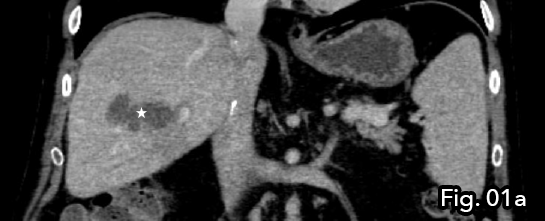

CT demonstrated intrahepatic blood flow via arterial collateralisation secondary to occlusion of the hepatic artery at the level of anastomosis proper as well as occlusion of the conduit vessel. A multiloculated, peripherally enhancing lesion with a low density centre and single gaseous loculation was seen in segments V and VIII of the liver. Due to the acute onset of clinical symptoms and new imaging findings, abscess formation secondary to ischemic liver disease was concluded (Fig 1a and 1b).

Fig 1a: Abscess formation was seen within the liver, indicating abscess formation secondary to ischaemic liver disease (star).

Figure 1b: Note the multiloculated/ spectated nature of the low density lesion (star) with gaseous loculation seen in the non-gravity dependent portion of the abscess (arrow).